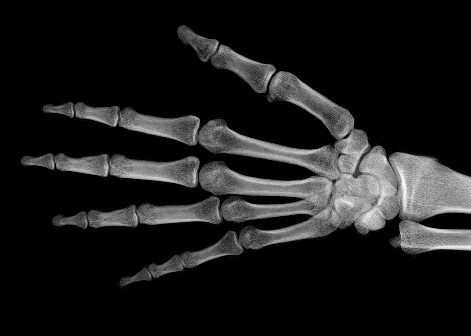

In the third experiment, we applied our method on a hand X-ray image data set (RSNA), which contains more than 10,000 hand X-ray images. And the image has high resolution (usually larger than 1514×2044151420441514\times 2044). These images are collected from clinical applications. Therefore, we can apply our method on these practical images, showing the efficiency and effectiveness of our method on real high resolution images.

In each panel of Fig. 10, the input image (left) is decomposed into soft tissue (middle) and bone image (right) by our method. Although we only show the first ten images from the data set, the results for the rest images are similar.

The bone images have better image contrast since the parameter α1𝛼1\alpha\geq 1 is theoretically guaranteed. Such enhancement can also be directly told by radiologists. Such enhancement is good for bone diagnosis in practical applications.

Moreover, the running time of our method on such high resolution images is less than half second in the MATLAB language on a laptop. Therefore, it can achieve higher performance on a better hardware in real applications. If higher performance is required, our model can be solved by the parallel Laplace equation solver on a modern graphic process unit (GPU), which usually has thousands of cores.

Refer to caption

(a) resolution 2044×1514204415142044\times 1514, run time 0.35s, α=1.34𝛼1.34\alpha=1.34

(b) resolution 2044×1514204415142044\times 1514, run time 0.35s, α=1.39𝛼1.39\alpha=1.39

(c) resolution 2044×1514204415142044\times 1514, run time 0.35s, α=1.63𝛼1.63\alpha=1.63

(d) resolution 2044×1514204415142044\times 1514, run time 0.35s, α=2.42𝛼2.42\alpha=2.42

(e) resolution 2044×1514204415142044\times 1514, run time 0.35s, α=2.31𝛼2.31\alpha=2.31

(f) resolution 2044×1514204415142044\times 1514, run time 0.35s, α=3.61𝛼3.61\alpha=3.61

(g) resolution 2044×1514204415142044\times 1514, run time 0.35s, α=3.02𝛼3.02\alpha=3.02

(h) resolution 2044×1514204415142044\times 1514, run time 0.35s, α=1.47𝛼1.47\alpha=1.47

(i) resolution 2044×1514204415142044\times 1514, run time 0.35s, α=2.11𝛼2.11\alpha=2.11

(j) resolution 2570×2040257020402570\times 2040, run time 0.58s, α=2.34𝛼2.34\alpha=2.34

Figure 10: From left to right in each panel: input X-ray images (left), our estimated soft tissue (middle) and estimated bone image (right). The resolution, running time of our algorithm and parameter α𝛼\alpha are provided. For these practical images, our method requires about half second to achieve the bone and soft tissue decomposition task in MATLAB language on a laptop. Higher performance can be achieved by C++ language on a better hardware.